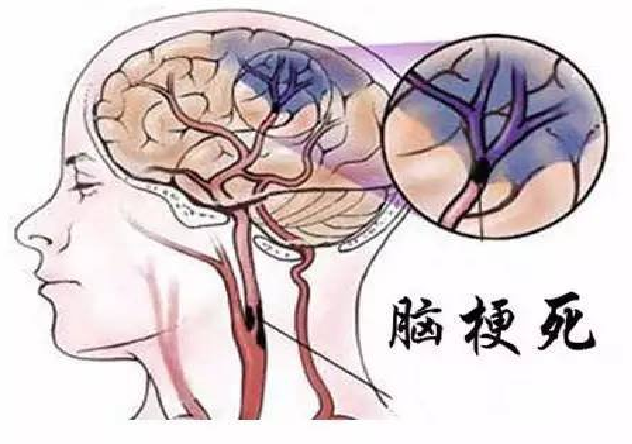

颈动脉粥样硬化和脑梗死

脑梗的病程

这个才16岁的花季少女,她的同型半胱氨酸这么高(≧10μmol/L为高血同),估计她的动脉粥样硬化已经起步n年了。如果现在不开始加以控制的话,估计她在40岁左右就会出现心梗或脑梗。

动脉粥样硬化当然会造成血管狭窄,甚至发生堵塞。如果只是阻塞小的血管,不重要器官的血管倒不致命,只是血脉不通,总感到疼痛不适。常言道:通则不痛,不通则痛。但如果是至关重要的血管发生阻塞,那可就要了命了。